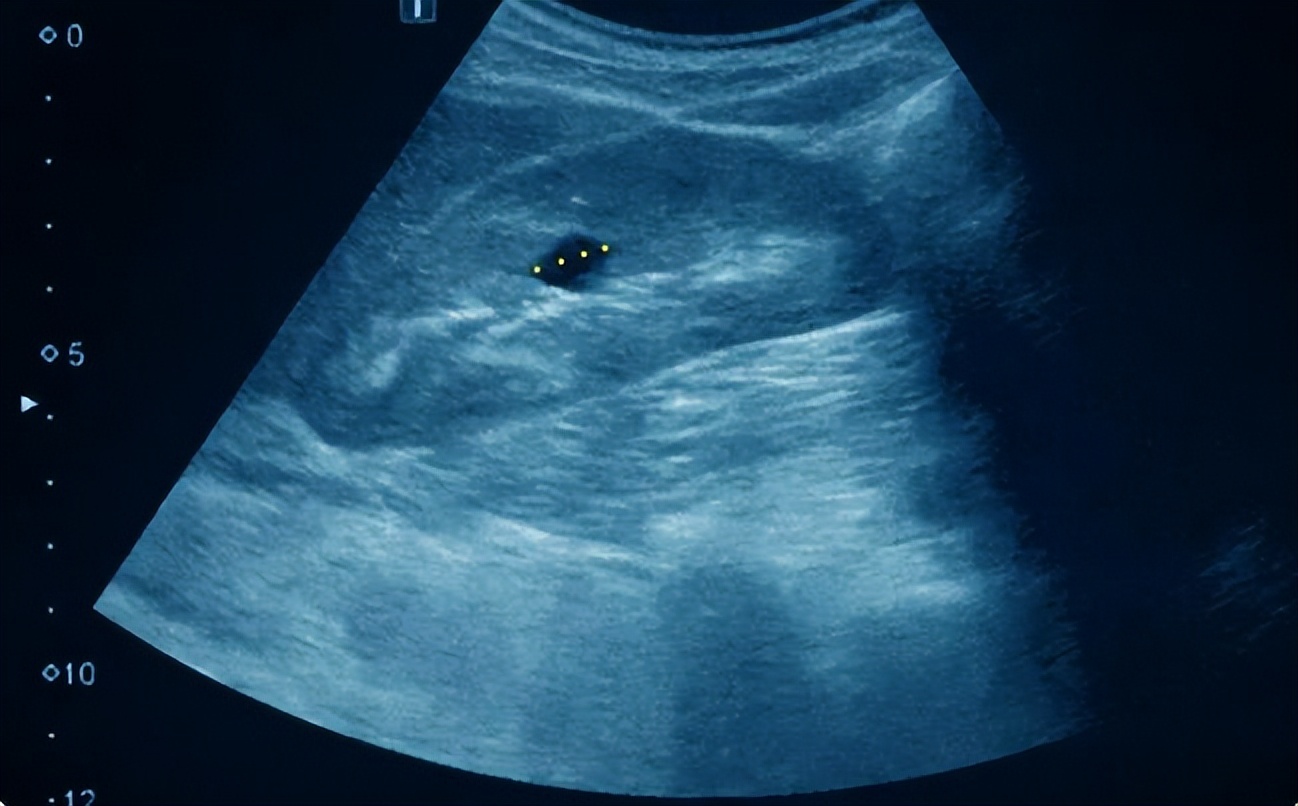

2、肝囊肿

如果患者患有肝囊肿,他很容易感到肝区疼痛和腹胀,随着囊肿的增大,会发生继发感染,引起更剧烈的腹痛和发热,随着囊肿体积的增大,会影响肠胃,使患者无法进食,挤压心脏,容易引起心力衰竭,如果肝囊肿继续生长,还会造成胆总管受压,容易导致黄疸。

如果黄疸破裂,会引起囊内出血,然后急性腹痛,大多数肝囊肿患者可能没有明显症状,如果是正常的,不需要治疗,但是如果有明显症状或者影响肝功能,此时就要手术切除。